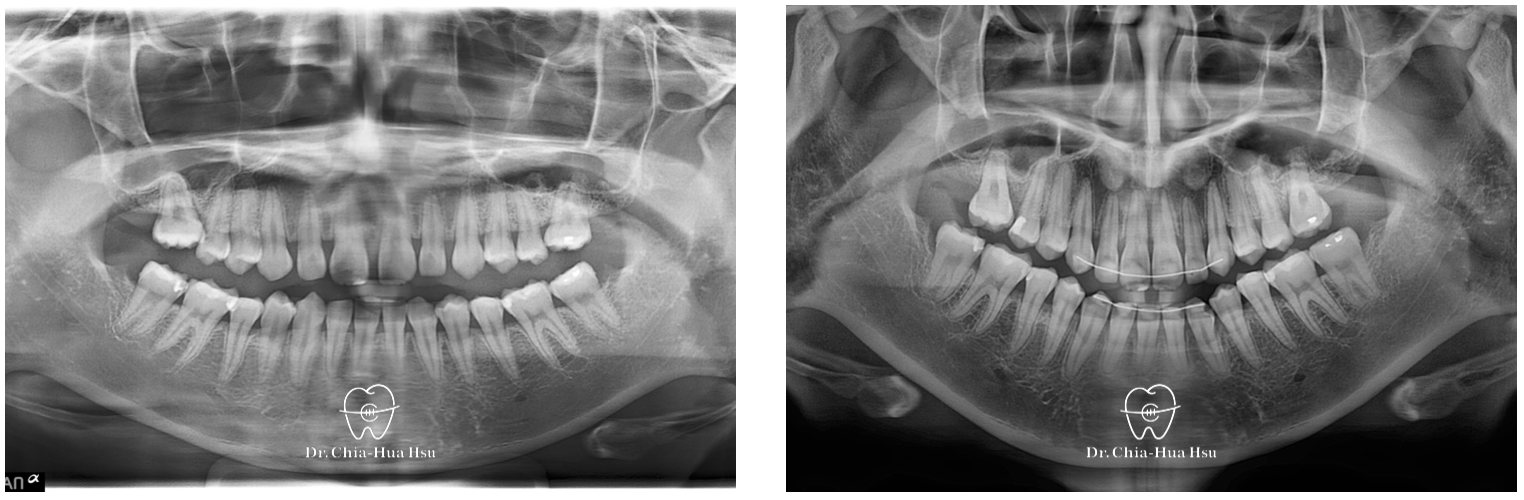

- 問題分析:患者除了暴牙、笑齦問題,有先天性缺失下顎門牙一顆以及上顎兩顆大臼齒,治療難度高。

治療前

治療後